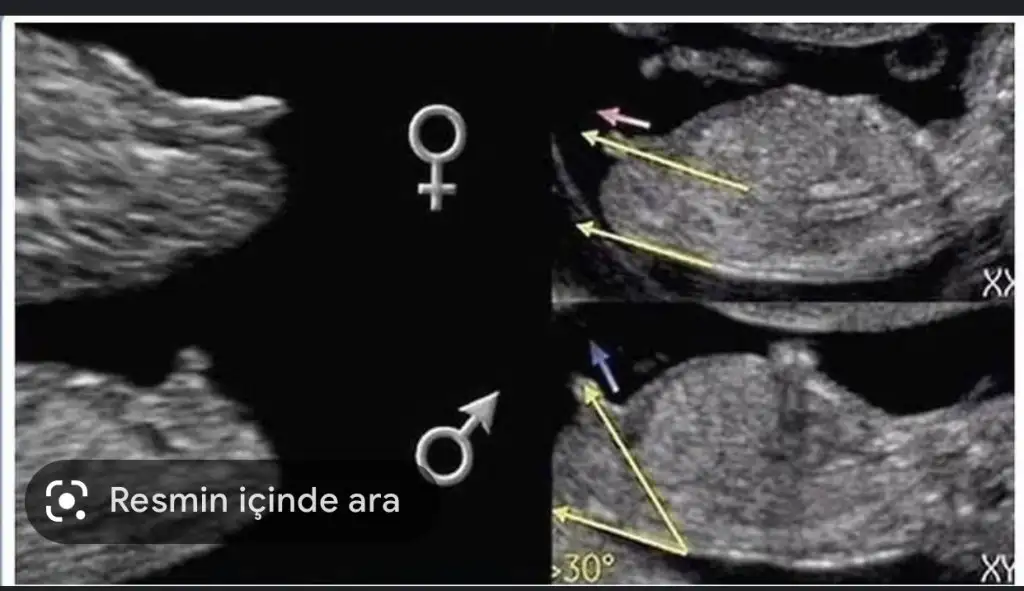

bu sıpalar hep boyle oluyor ama dimiBen kızımı 16 haftada öğrenmiştim. Rutin kontrolde. Oğlum hiç göstermedi doktor çok uğraştı ama sıpa o zaman da inatmış23 te renkli ultrasonda öğrenmiştik. Göstermediği için biz hep kız demiştik